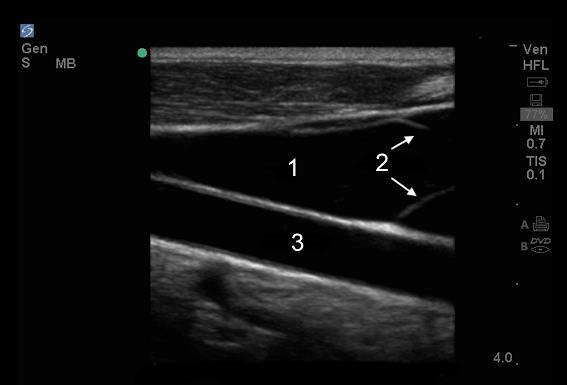

Vascular Internal Jugular Vein (IJV) Long Axis Image

1. Internal Jugular Vein (IJV)

2. Valves in IJV

3. Common Carotid Artery (CCA)